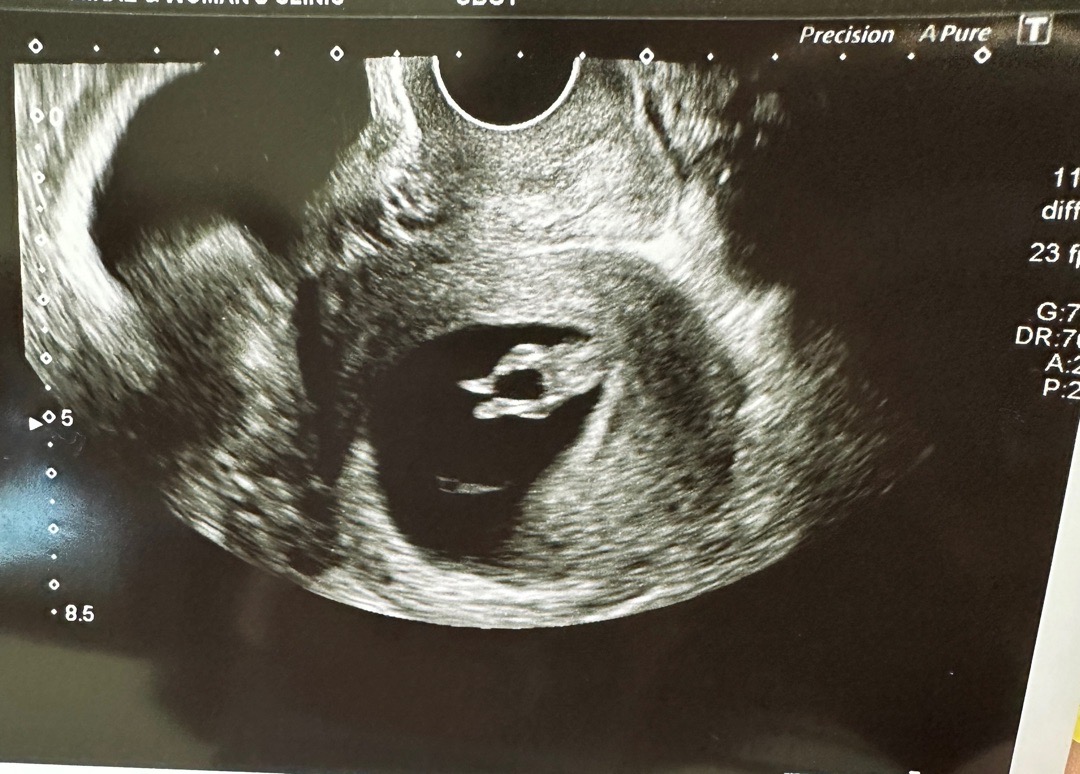

ㅋㅋㅋㅋㅋ알아서 잘 크더라구요 첫째 육아하느라 원래 잘 못챙겨먹는데 입덧하면서 더 굶었어요 근데 알아서 잘커주네요 12주차인데 7cm ㅎㅎㅎ

오늘 10주 3일 차로 애기보러 다녀왔는데.. 선생님께서 단거 먹고 왔어요??? 하시더라구요. 😄 애가 너무 활발하게 움직이더라구요 ㅋㅋㅋㅋㅋ 팔다리를 휙휙~~ 아이는 4cm 더라구요.^^ 검진하면 초음파 사진을 두장 주시는데 그 중 한장이 다리만 있는 사진을 출력하시면서 다리 너무 귀엽지 않냐고 좋아시더라고요ㅎ 의사선생님 취향인 다리 사진 올려 보아요 입덧도 그동안 못먹고 힘들었던것도 아기 보고나니 그냥 좋더라구요 ㅎ 입덧 있으신분들 힘내세요. 나도 힘!